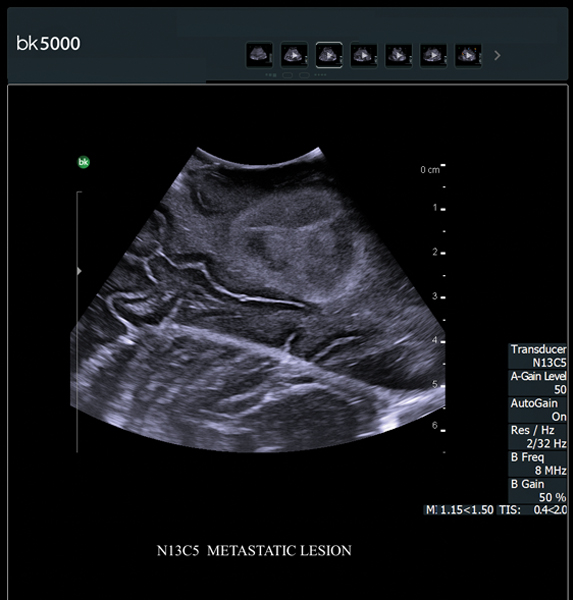

- Ngoài ứng dụng hình ảnh siêu âm chẩn đoán thông thường thì Đặc biệt được sử dụng trong phẫu thuật:

+ Điều trị Hủy u gan dưới hướng dẫn của siêu âm: Bằng sóng cao tần (RFA), Microwave ablation, sinh thiết gan, chọc hút dẫn lưu gan...